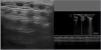

The usual evolution of pulmonary patterns in neonates delivered before 32 weeks starts with a pattern characteristic of RDS at birth, with high LUS score values in the first days, but then normally improve thereafter as the primary surfactant deficiency resolves, reaching LUS score values near 0 at around 1 week post birth.38 The patients whose LUS scores do not exhibit this decrease or actually increase are more likely to develop BPD (Fig. 6). On the other hand, in preterm infants born before 28 weeks, this decrease in the LUS score delays, even after the initial surfactant deficiency stage has passed, to up to 4 weeks post birth39–41 (Table S4).

Sonographic evaluation in the first week of life in preterm neonate born at 25 weeks whose mother developed chorioamnionitis and was a carrier of Ureaplasma parvum in cervical fluid. (A) Normal pattern at 4 h post birth. (B) Day 3 post birth: alveolar-interstitial pattern with pleural thickening and fragmentation of the pleural line only in posterior fields. (C) Week 1 post birth: the same abnormal features are visible in every lung field. At this point, the respiratory support needs of the patient did not increase significantly, but starting from 2 weeks post birth she required aggressive scalation of ventilatory parameters and eventually developed severe bronchopulmonary dysplasia.